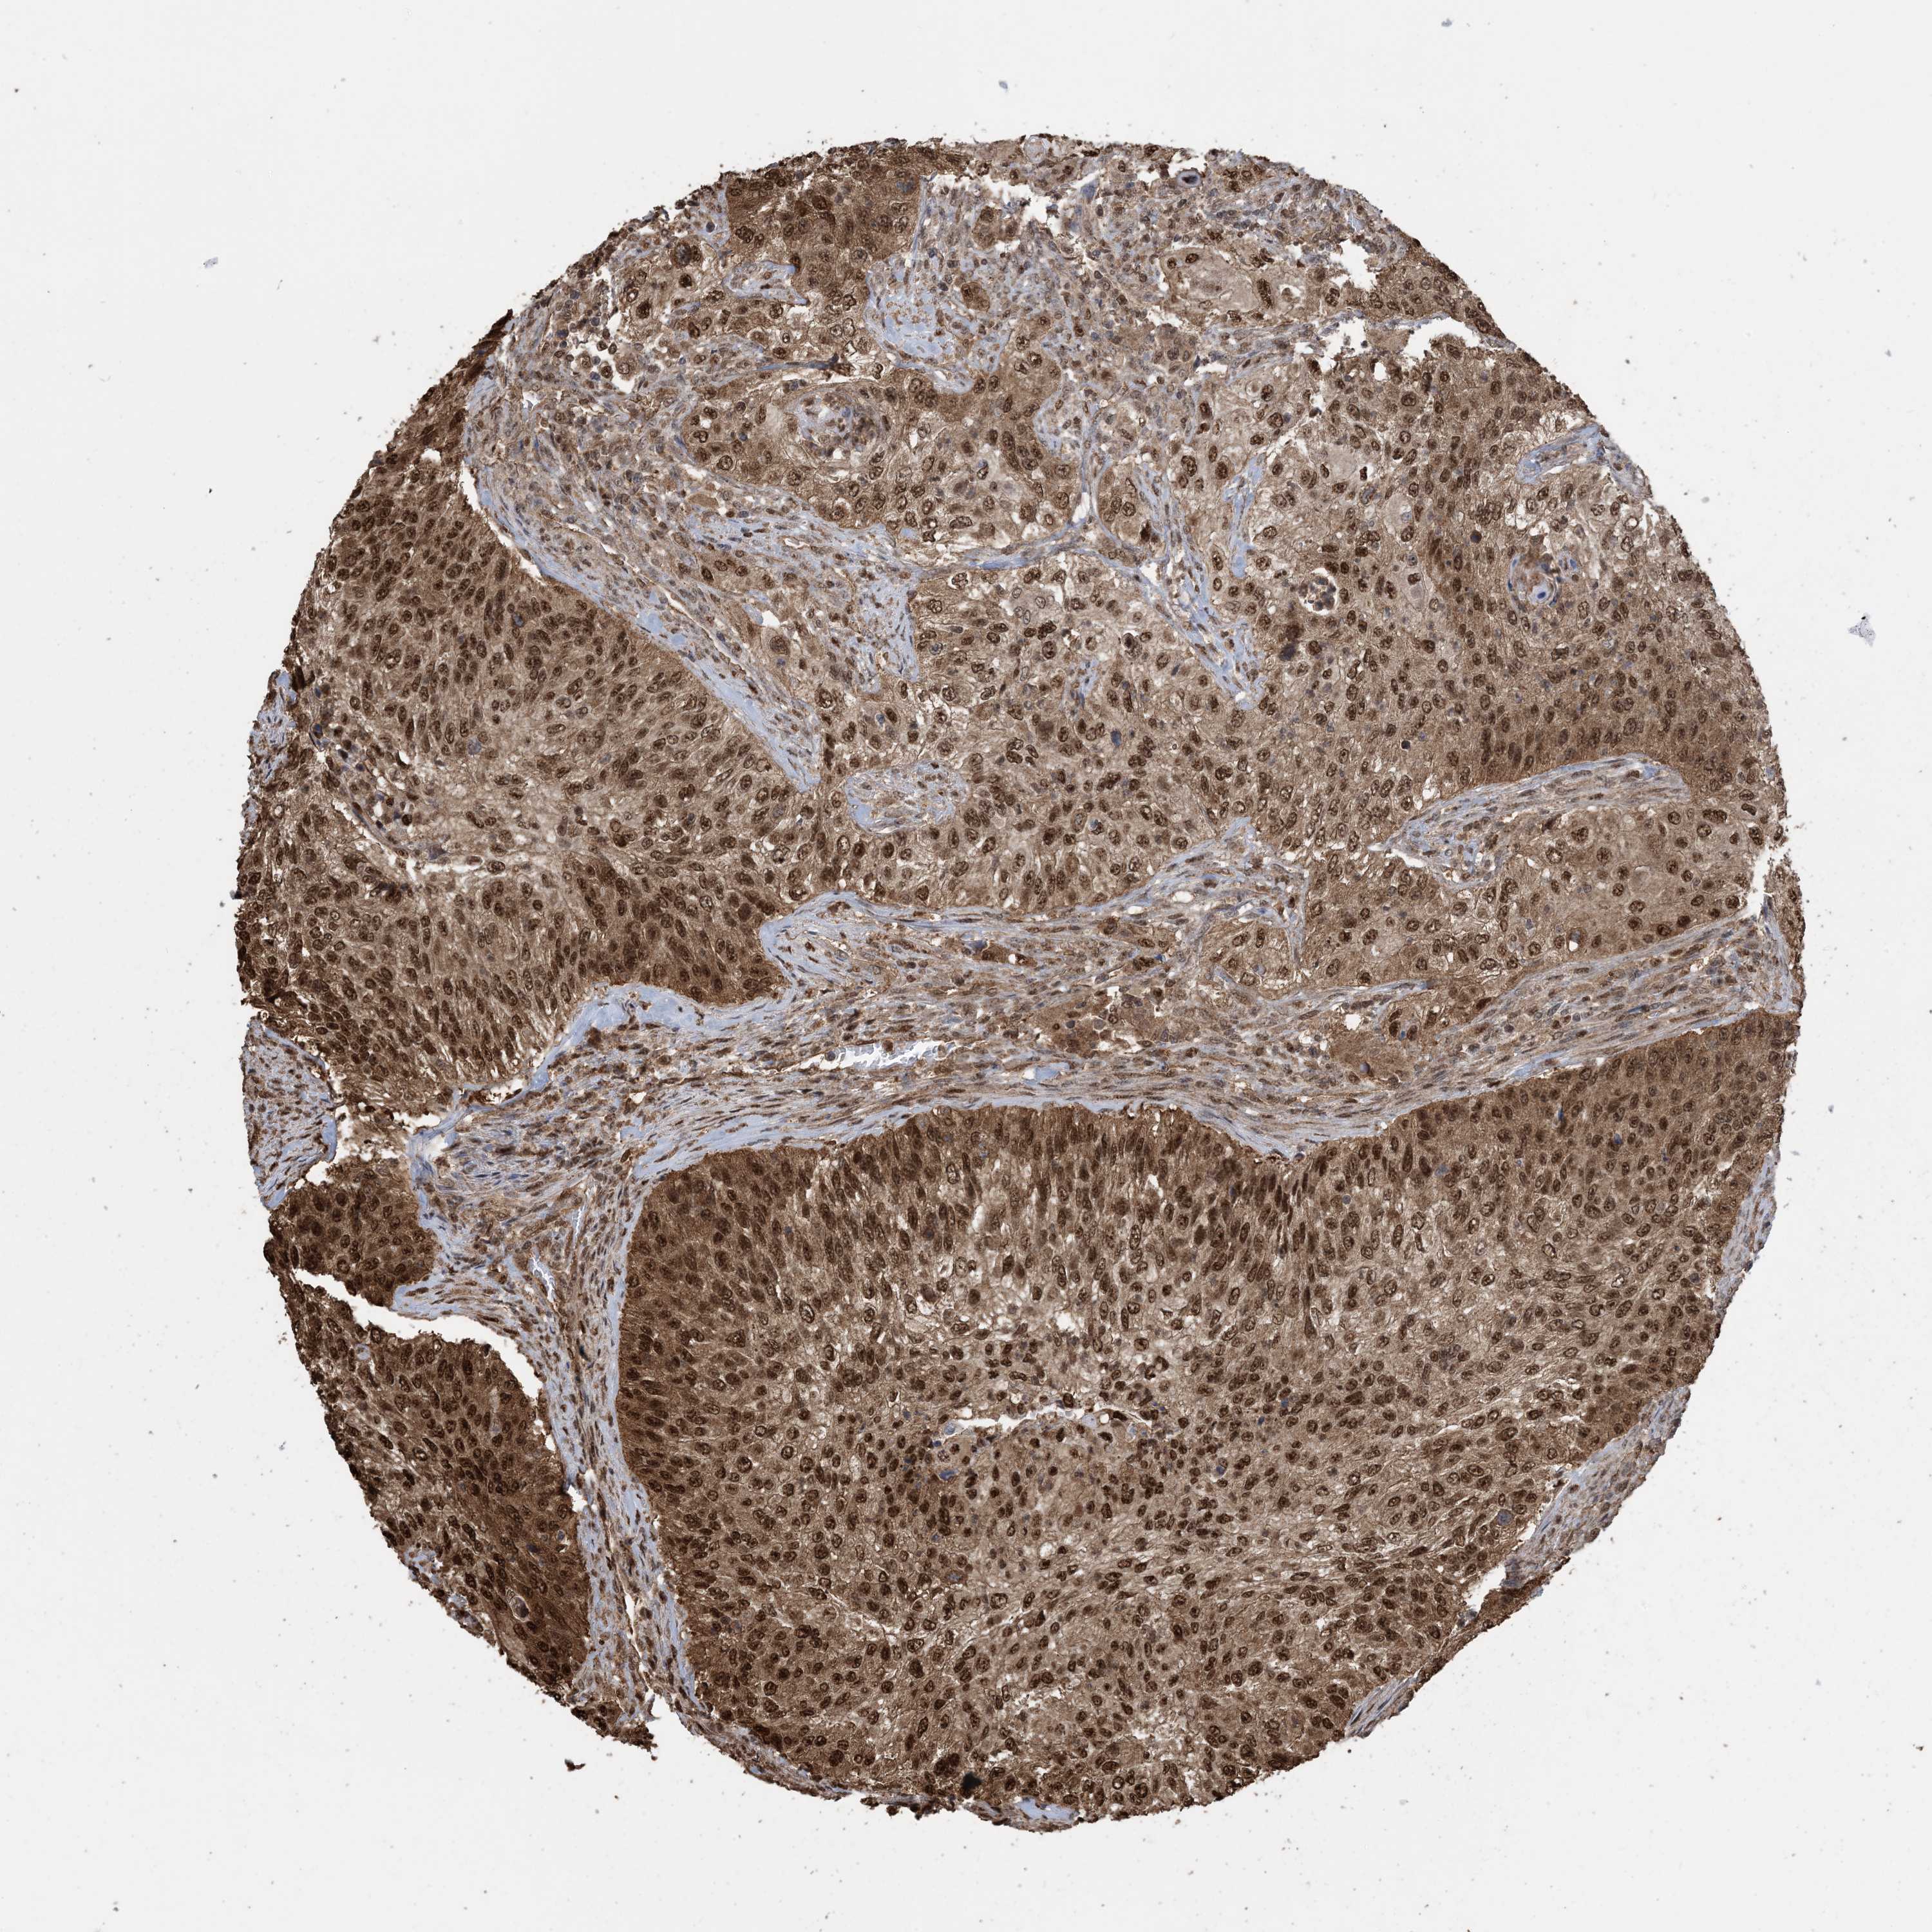

UROTHELIAL CANCER - Protein expressioni

A mouse-over function shows sample information and annotation data. Click on an image to view it in a full screen mode. Samples can be filtered based on level of antibody staining by selecting one or several of the following categories: high, medium, low and not detected. The assay and annotation is described here.

Note that samples used for immunohistochemistry by the Human Protein Atlas do not correspond to samples in the TCGA dataset.

Antibody stainingi

Antibody staining in the annotated cell types in the current human tissue is reported as not detected, low, medium, or high, based on conventional immunohistochemistry profiling in selected tissues. This score is based on the combination of the staining intensity and fraction of stained cells.

Each image is clickable and will lead to virtual microscopy that enables deeper exploration of all samples and also displays staining intensity scores, fraction scores and subcellular localization as well as patient and tissue information for each sample.

Antibody HPA052504

Antibody CAB017451

Antibody CAB032815

Staining

High

Medium

Low

Not detected

Intensity

Strong

Moderate

Weak

Negative

Quantity

>75%

75%-25%

<25%

None

Location

Nuclear

Cytoplasmic/membranous

Cytoplasmic/membranous,nuclear

Urothelial carcinoma, High grade

Urothelial carcinoma, NOS

Urothelial carcinoma, Low grade